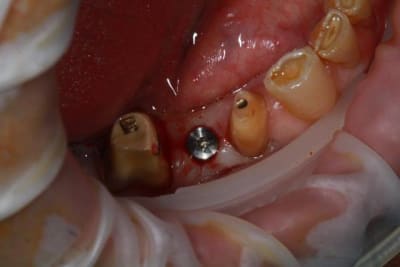

Nouveau patient, pose d'un implant il y a 2 mois....échec sans raisons particulières, douleurs et dépose.

Ce matin repose d'un nouvel implant et comme je ne veux pas prendre de risque, et que les dents adjacentes doivent être couronnées, je pose un bridge en emax press, mais scellé au ciment provisoire...

Si l'implant va bien le bridge sera déposé, coupé, et 44/46 seront collées définitivement après traitement acide et silane.

Si par hasard l'implant pose problème, dépose et bridge collé.